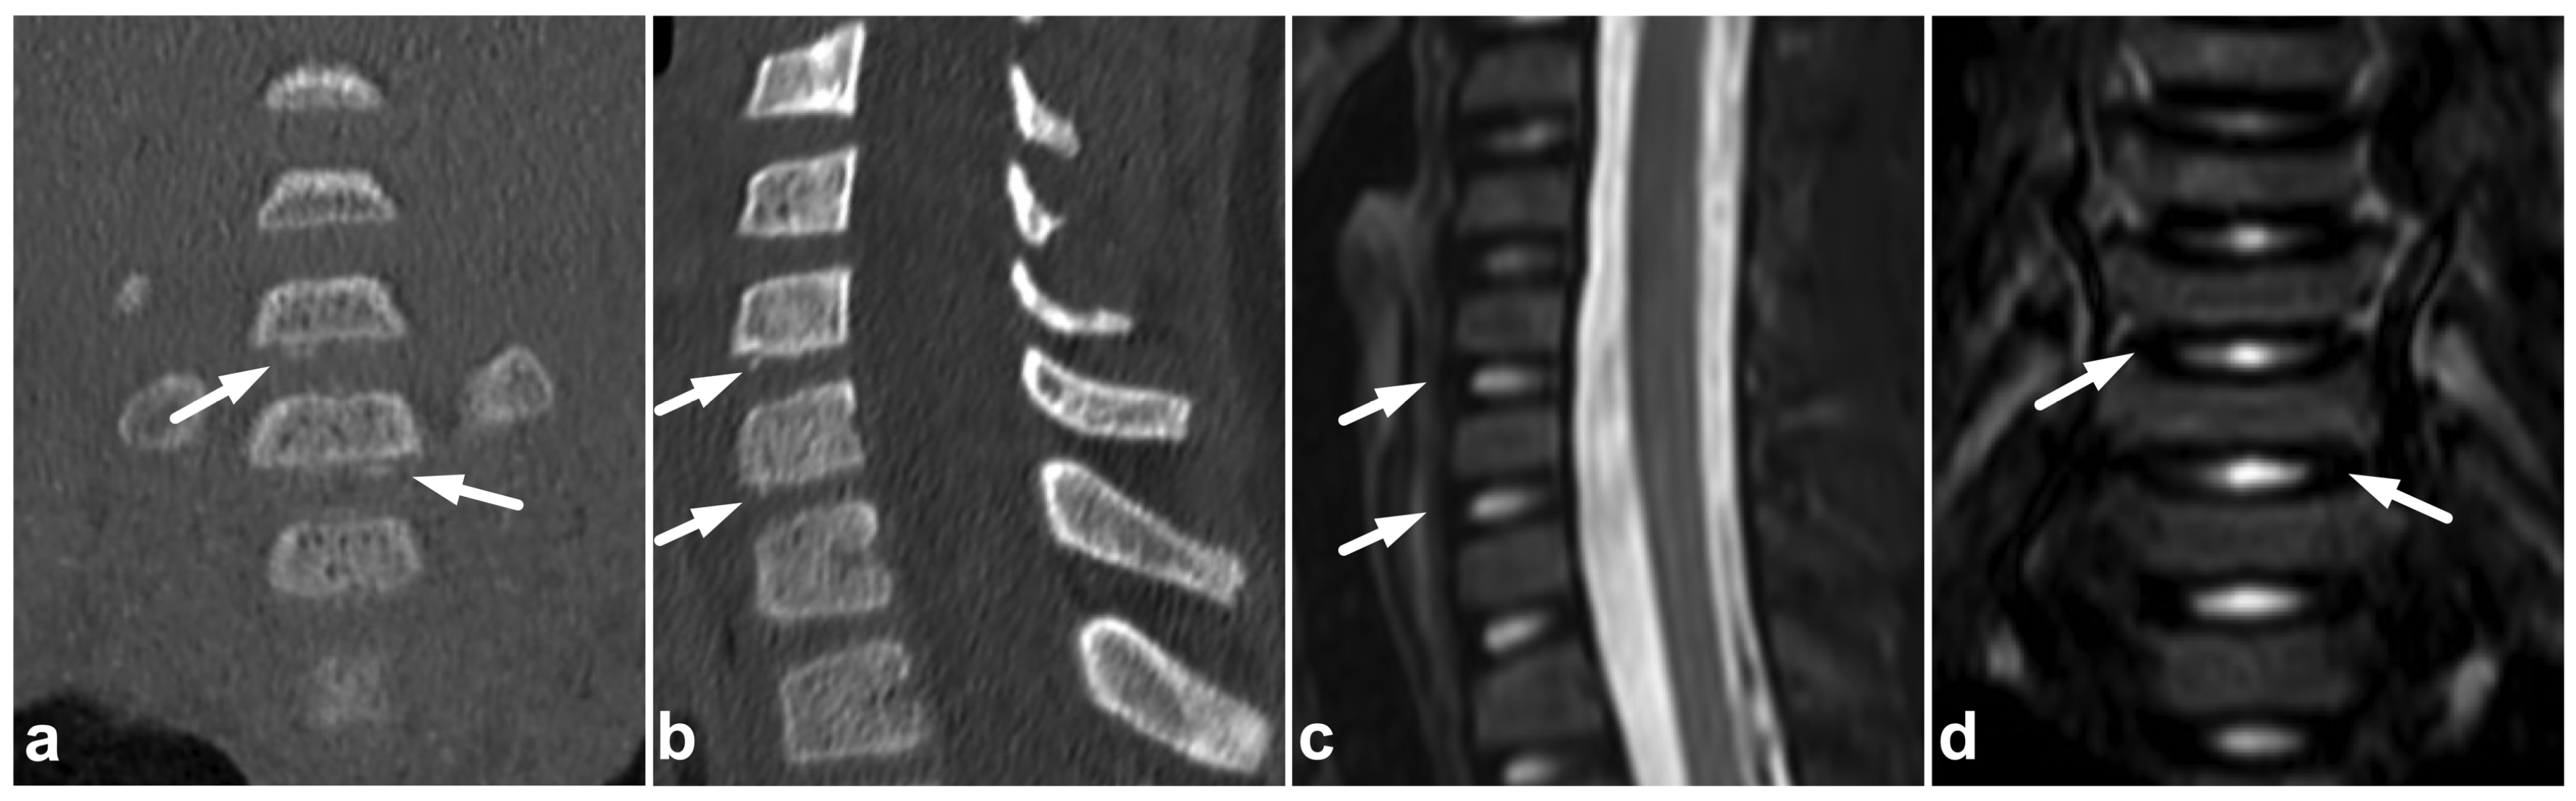

6. Spinal Cord Injuries

The use of MRI in acute spinal cord trauma was first described in 1983 [60,61] and it has been the gold standard in imaging these injuries ever since. T1-weighted, T2-weighted, and STIR sequences are the cornerstones in assessing the cord [49]. Diffusion-weighted imaging (DWI) and diffusion tensor imaging (DTI) might be useful in detecting subtle injuries and as a prognostic biomarker, but their role in clinical practice is not fully established yet [62,63,64,65,66]. Susceptibility-weighted imaging (SWI) or T2*-weighted sequences might increase the sensitivity in the case of small intramedullary hemorrhages but are technically challenging to obtain due to pulsation and motion artifacts [67,68]. Cases of spinal cord injuries are presented in Figure 15 and Figure 16.

Figure 15.

(a) Sagittal T2-weighted. (b) Sagittal T1-weighted. (c) Sagittal T2-weighted fast field echo. (d) Coronal STIR. (e) Axial T2-weighted, level of the lower end plate of C6 (caudal dotted line in the image (b)). (f) Axial T1-weighted, level of the lower end plate of C6 (caudal dotted line in the image (b)). (g) Axial T2-weighted, level of the lower end plate of C5 (cranial dotted line in the image (b)). (h) Axial T1-weighted, level of the lower end plate of C5 (cranial dotted line in the image (b)). A 17-year-old male after diving into shallow water. The spinal cord is edematous approximately from the level of the lower end plate of C4 to the lower end plate of C6 (black arrowheads). There is a hemorrhagic contusion in the right-sided grey matter (white arrows) and a contusion without macroscopic hemorrhage on the left side (white arrowheads). Hematoma can be seen in the anterior epidural space (curved arrows). There are fractures of vertebral bodies and posterior arches of C5 and C6 (asterisks and small arrows).